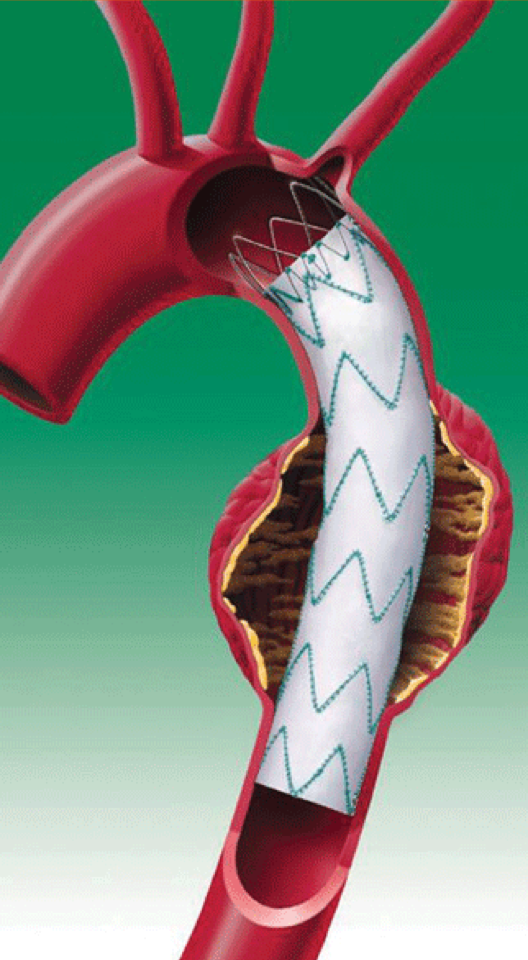

En fonction de la taille de ces anévrismes, de leurs localisations, il peut être proposé un traitement chirurgical. Il y a encore quelques années, ces anévrismes devaient être opérés en faisant de grandes ouvertures, par thoracotomie. Il s’agissait de chirurgies lourdes, parfois avec de nombreuses complications, nécessitant du temps pour récupérer. L’amélioration des prothèses disponibles fabriquées par l’industrie, a permis le développement de prothèses déployées par voie endovasculaire. On parle d’endoprothèses thoraciques ou TEVAR (Thoracic Endo Vascular Aortic Repair). Le concept est de monter sur un stent une prothèse d’où le nom d’endoprothèse couverte. Cette endoprothèse va venir exclure l’anévrisme, limitant ainsi le risque de croissance de ce dernier et donc de rupture.

Dans la grande majorité des cas, la voie d’abord se fait par voie fémorale, sans aucune incision, de manière percutanée. Il sera nécessaire d’injecter de l’iode durant la procédure pour réaliser une angiographie et permettre ainsi le déploiement au bon endroit de la prothèse. La procédure est courte d’environ 1H. Cependant, parfois, en fonction de l’extension proximale de l’anévrisme, il n’est pas rare de devoir faire un pontage entre l’artère carotide et l’artère sous-clavière gauche (pontage carotido-sous-clavier gauche), car le déploiement de l’endoprothèse peut nécessiter d’obturer cette dernière pour garantir un bon résultat. Dans les cas les plus simples, vous resterez hospitalisé(e) une nuit après l’intervention avant votre retour à domicile.